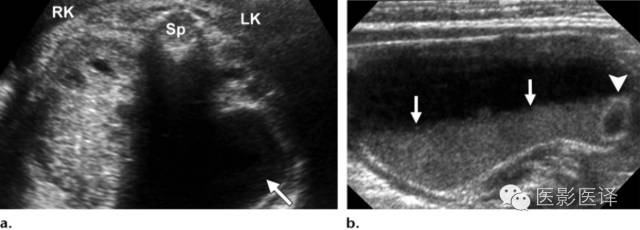

超声检查中,复杂性卵巢囊肿是厚壁的,且回声不均质。图像特征包括多个分隔(图4、5)、内部移动性高回声、实性表现(图6),或液液平面(图5、7)。复杂性囊肿被认为是扭转的结果,胎儿比新生儿更常发生。出现复杂性囊肿的表现高度提示需要手术。与胎儿卵巢囊肿伴发的其他影像表现包括羊水过多和腹水,可能是由于漏出或囊肿破裂所致。肠管或肾脏的继发梗阻被认为是扭转时卵巢坏死引起的粘连所致。

图7 囊肿中的液液平面。(a)轴位胎儿超声图像显示在左肾(LK)前方一个孤立性囊性肿块(箭),脊柱(Sp)另一侧可以看到正常的右肾(RK),三周后的随访图像(未展示)显示团块中出现液液平面。(b)新生儿经腹长轴位图像显示一个薄壁囊性团块,有液液平面(箭),子囊(箭头)是卵巢囊肿的确诊征象。(c)新生儿矢状位T2WI显示一个出血性卵巢囊肿,有液液平面(箭)和低信号血液成分。